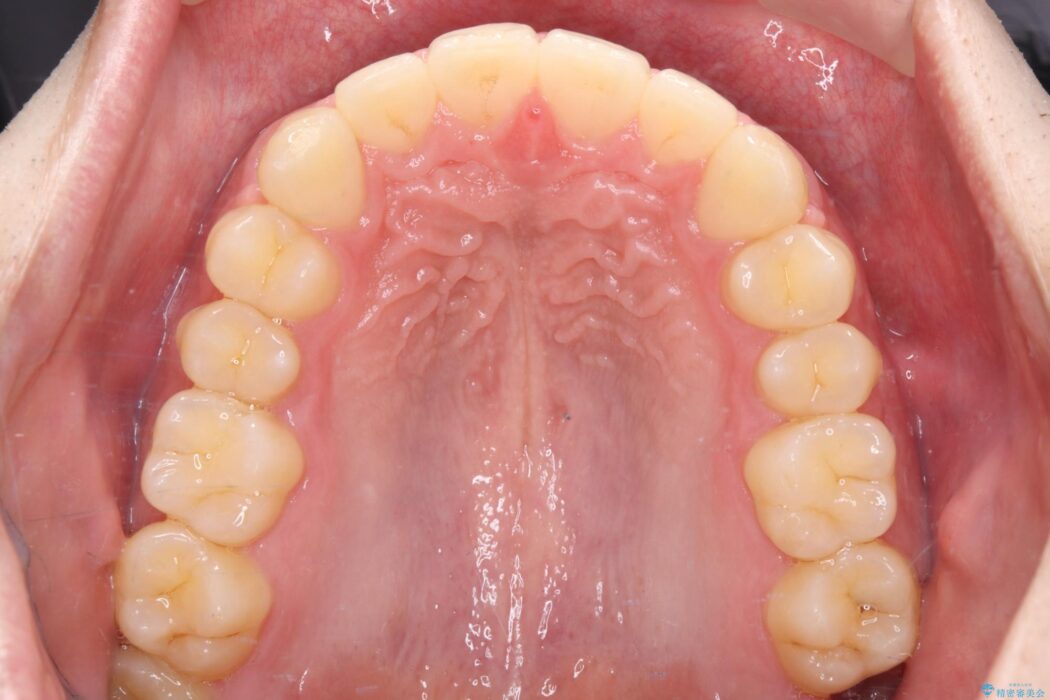

上の前歯のすきっ歯を治したいとご来院された患者様です。

上顎中切歯間の隙間の他にもフロスが抵抗なく入るスペースが上顎は数か所ありました。スペースを閉じ下顎の歯列弓との調和をとるためIPRを行いました。